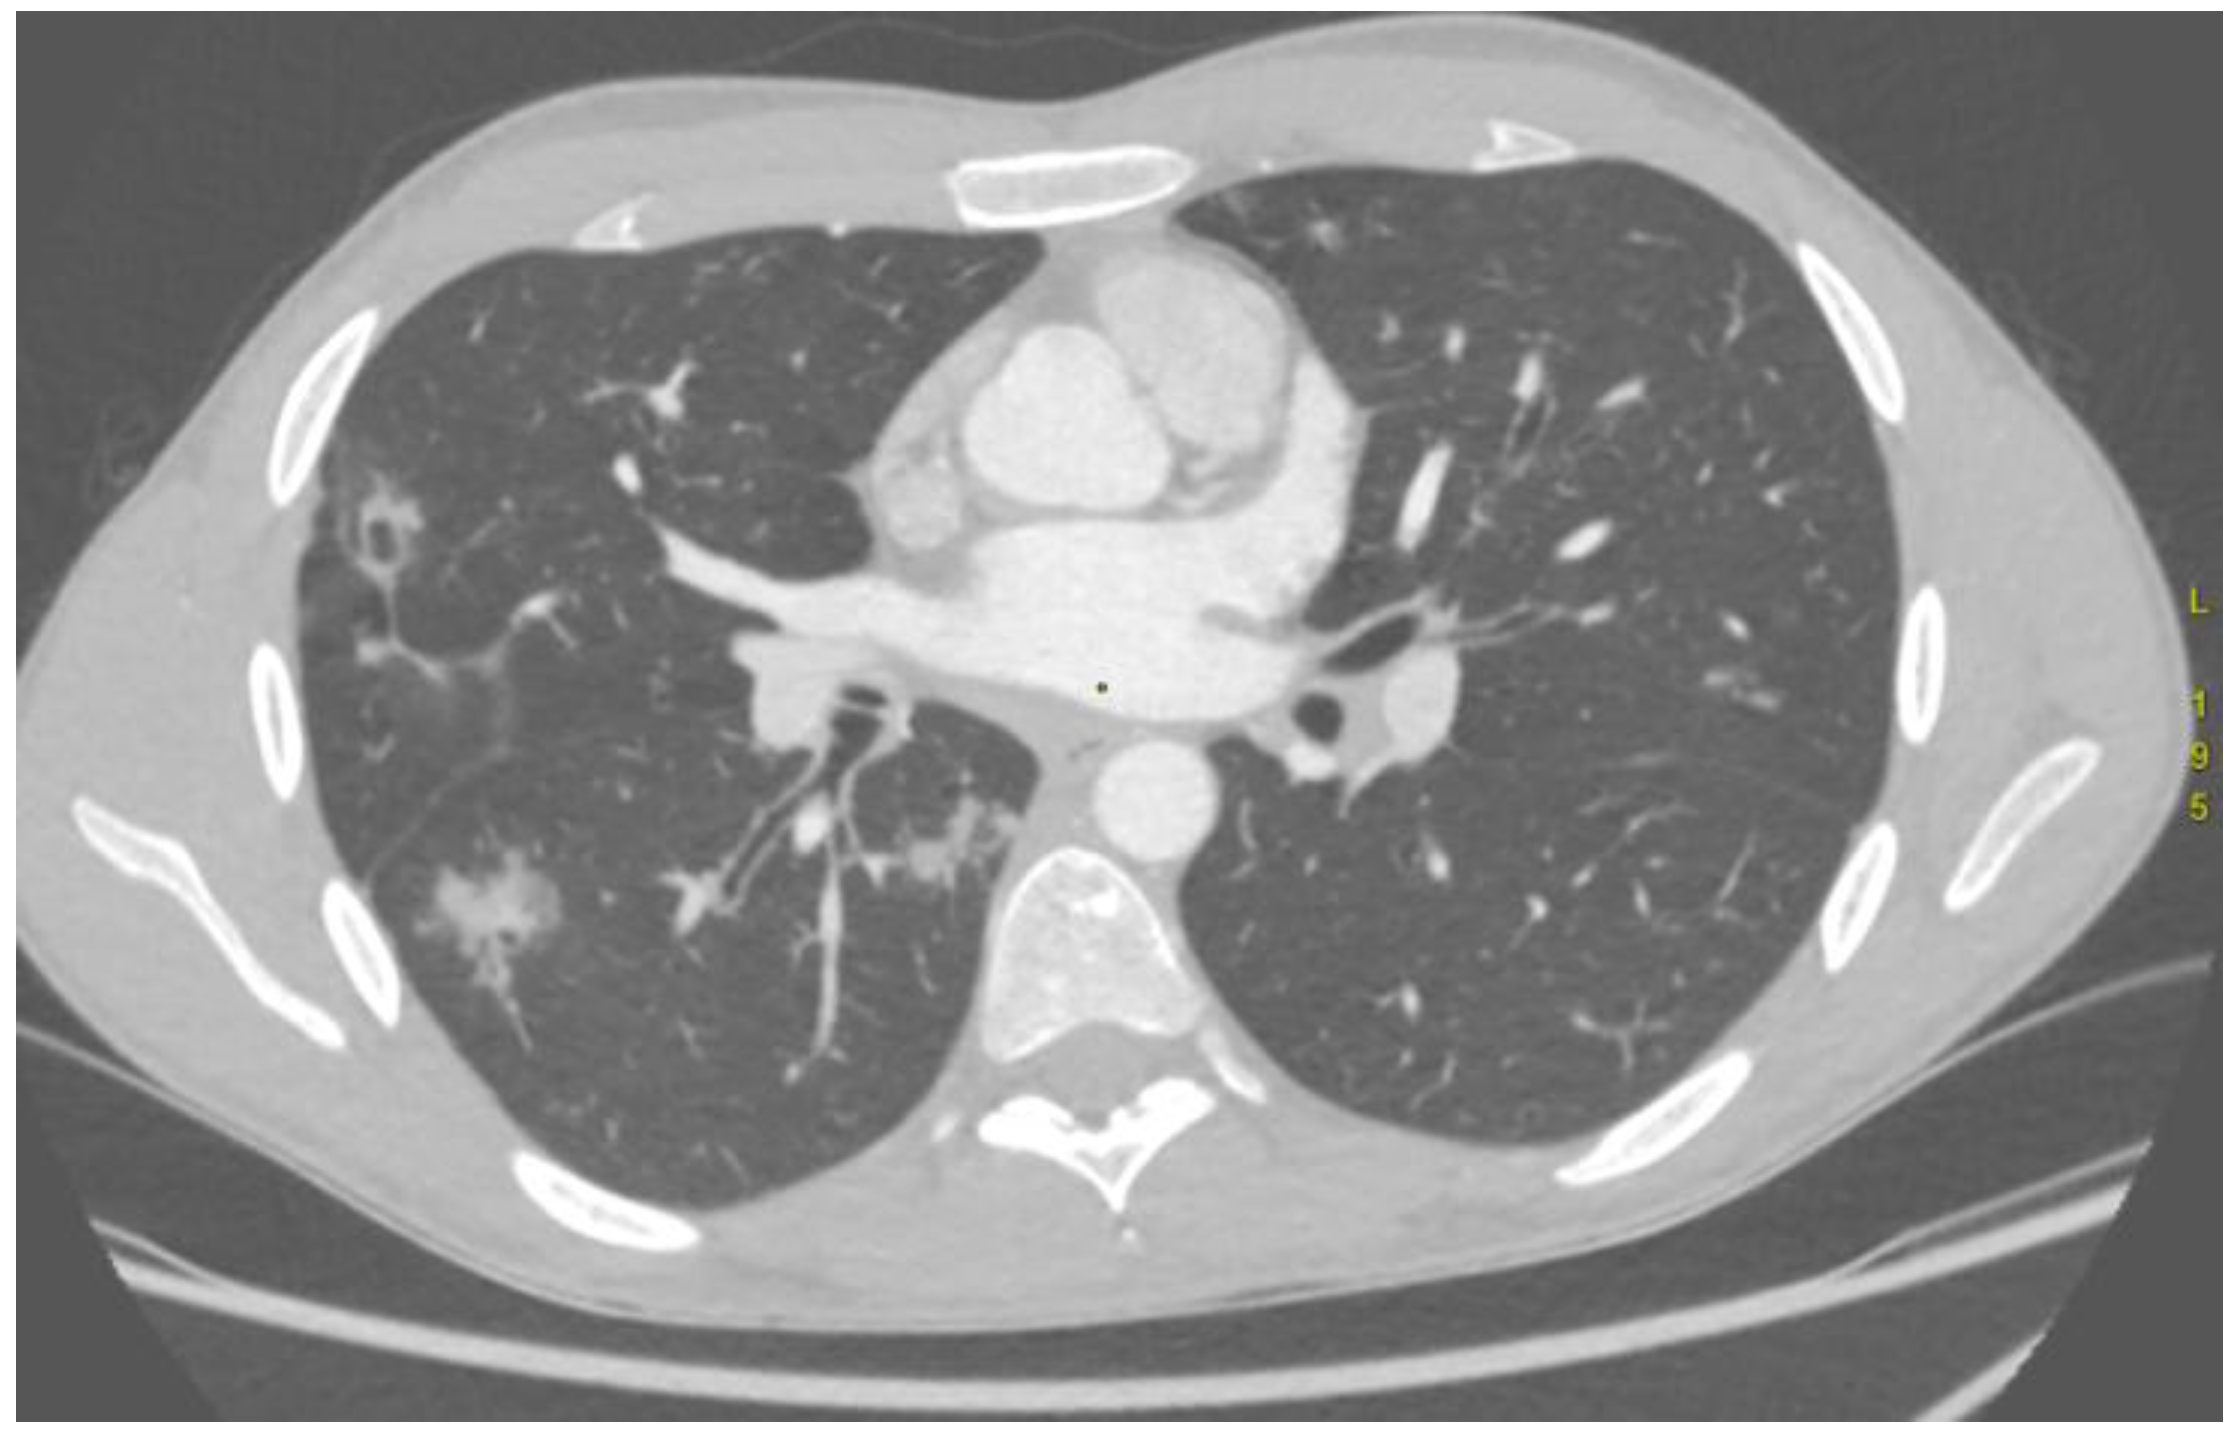

| P10 | GGO in S3 of RUL | 2 × R BA | Yes |